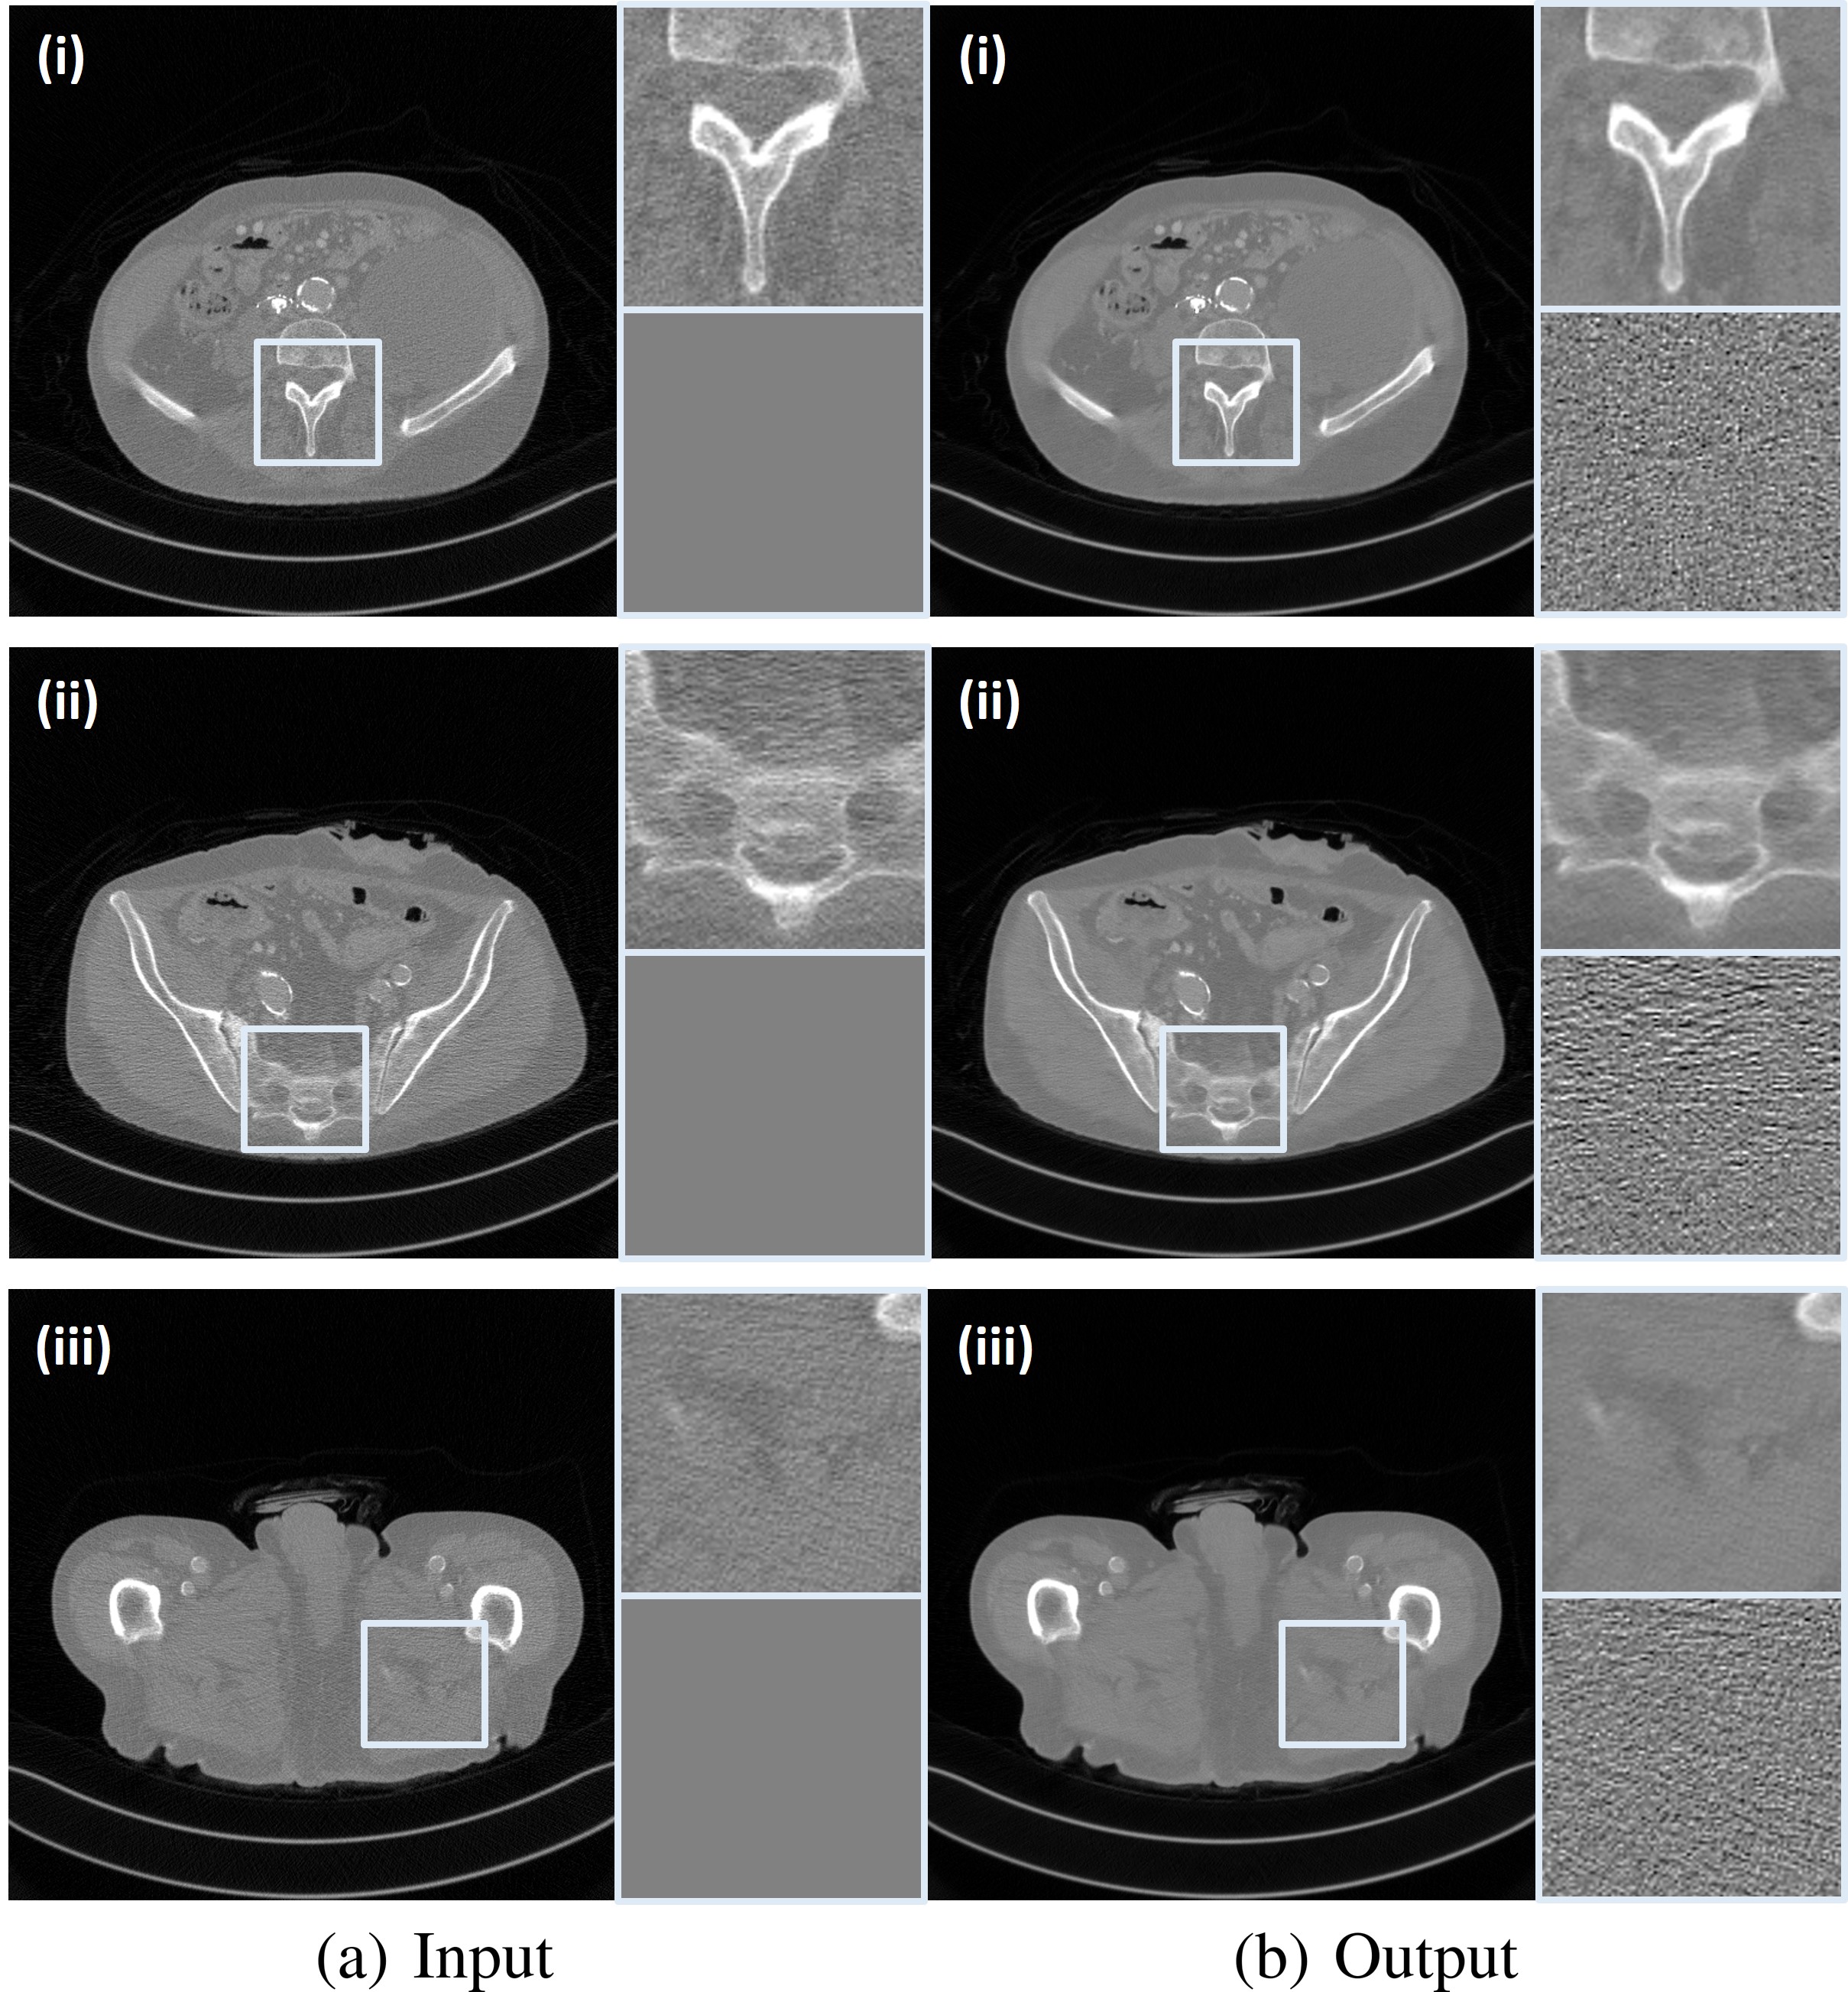

In Fig. 10, there are three representative denoising results by the proposed CycleGAN with an invertible generator to verify the noise reduction performance qualitatively. The gray boxes in the input low-dose CT images and the denoising result images are enlarged in order to more accurately visualize the noise reduction performance, and their difference from the input are also visualized. The difference images clearly show the removed noise components. As can be seen from Fig. 10, the proposed method removes noise components evenly without any structural information loss. Therefore, it distinguishes bone and each soft tissue more clear.